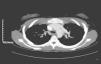

Mujer de 19 años con SMRKH, que refería catarros frecuentes, presentaba febrícula, expectoración purulenta y disnea de mínimos esfuerzos. La exploración física era normal, salvo leve taquipnea y crepitantes inspiratorios bibasales. En la analítica presentaba leucocitosis con neutrofilia y en la gasometría arterial (aire) mostraba pCO2 de 39 y pO2 de 57. La radiografía de tórax y el electrocardiograma eran normales. En la tomografía computarizada (TC) torácica y la resonancia magnética (RM) se objetivó drenaje venoso pulmonar anómalo parcial: la vena del lóbulo superior izquierdo drenaba en la vena innominada a través de la vena vertical (figs. 1 y 2). El ecocardiograma transtorácico con contraste descartó comunicaciones intracardiacas, así como sobrecarga de cavidades derechas.

El SMRKH es una rara malformación (incidencia de 1/4.000 recién nacidas vivas) caracterizada por agenesia congénita de útero y vagina en mujeres con ovarios, caracteres sexuales secundarios y cariotipo normales1–4. La etiopatogenia radica en una falta del desarrollo de los ductos müllerianos, con la consecuente alteración de las estructuras derivadas de ellos1. El diagnóstico se hace por amenorrea primaria e incapacidad de penetración vaginal, confirmándose por ultrasonografía y RM1,4. Se divide en: típico o I (agenesia de útero y vagina) y atípico o II, asociado a otras malformaciones (renales, esqueléticas, sordera, digitales y cardiacas)1–4. Las malformaciones pulmonares asociadas publicadas son prácticamente anecdóticas; así, se ha descrito un caso de hipoplasia pulmonar4 y un caso de drenaje venoso pulmonar anómalo total3. Describimos un caso de drenaje venoso pulmonar anómalo parcial donde la vena del lóbulo superior izquierdo drena en la vena innominada a través de la vena vertical. El drenaje venoso pulmonar anómalo se produce cuando la sangre venosa pulmonar de una o más venas desemboca directamente en la aurícula derecha o en las venas sistémicas. Puede ser total (4 venas anómalas) o parcial (1-3 venas anómalas). En ambas formas se produce shunt extracardiaco izquierda-derecha, provocando aumento del flujo sanguíneo con la consiguiente sobrecarga en aurícula y ventrículo derecho, así como en arteria y venas pulmonares. Este hiperaflujo puede causar insuficiencia cardiaca e hipertensión pulmonar. La sobrecarga hemodinámica depende del número de venas con conexión anómala, de la localización del drenaje y de la asociación o no con comunicación intraauricular. Así, los pacientes pueden estar desde asintomáticos, presentar catarros frecuentes —como en nuestro caso— o llegar a presentar insuficiencia cardiaca e hipertensión pulmonar. La vena anómala en ocasiones puede verse en la radiografía simple, confirmándose el diagnóstico por TC y RM, y recurriendo al cateterismo cardiaco ante la sospecha de hipertensión pulmonar.